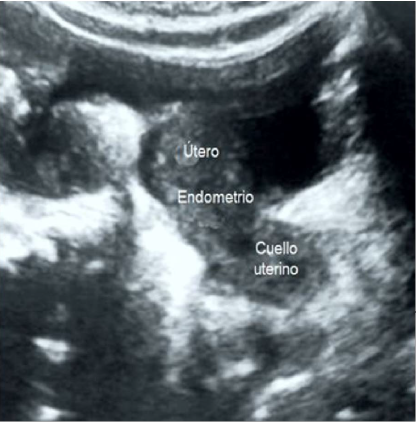

La ecografía pélvica demostró la presencia de tumores quísticos presentes en cada ovario, de paredes lisas, multiloculares, ecos internos gruesos y ausencia de porciones sólidas. El del ovario derecho medía 6 x 5 centímetros y el del izquierdo media 9 x 6 centímetros, con un volumen combinado de 257 mm. y puntuación de Sassone de 6 puntos (figura 1). El útero de aspecto normal, medía 3,2 × 2,0 centímetros con endometrio hiperecoico e intacto (figura 2). No se observaron otras patologías abdominales o pélvicas. La determinación de la edad ósea de la paciente era comparable a la de sujetos femeninos de 32 meses según la puntuación de Greulich-Pyle, por lo que fue considerada como normal. Las imágenes de resonancia magnética cerebral no mostraron lesiones o tumoraciones. En vista de los hallazgos se realizó el diagnóstico de pseudo-pubertad precoz debida a quistes foliculares ováricos autónomos bilaterales.